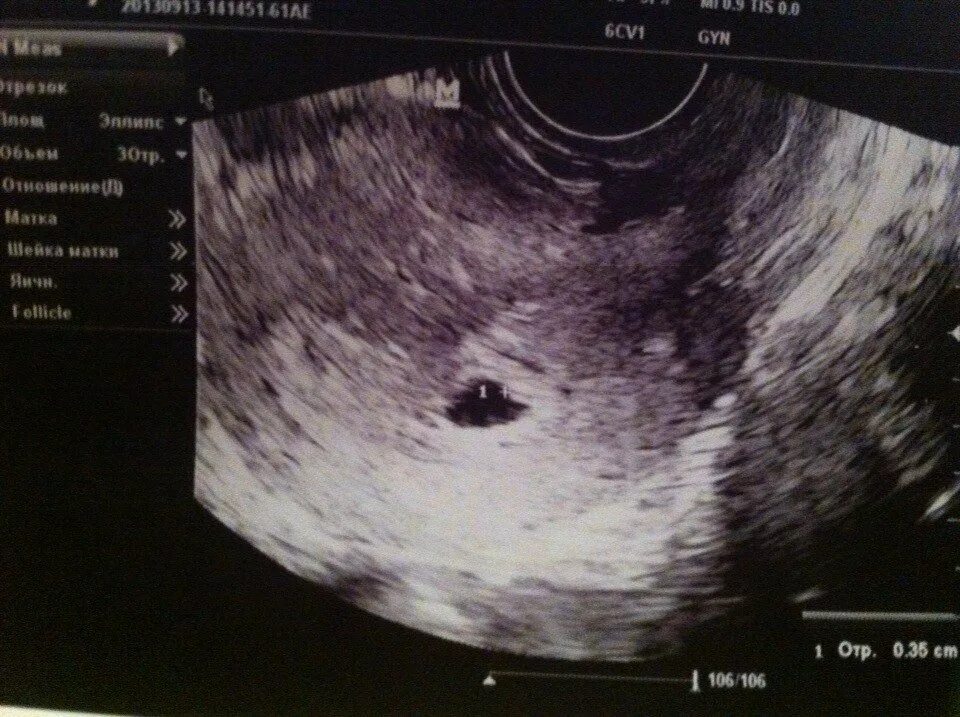

Не видно эмбриона на 6 неделе беременности